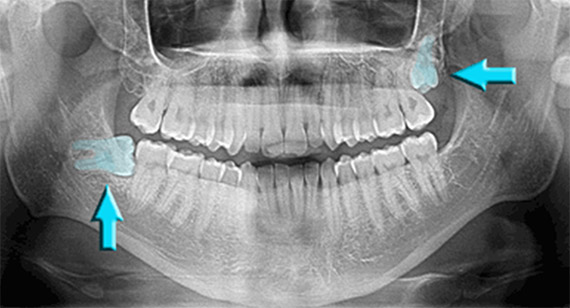

www.alamy.comImpacted Wisdom Teeth, X-ray - Stock Image - M782/0249 - Science Photo

www.alamy.comImpacted Wisdom Teeth, X-ray - Stock Image - M782/0249 - Science Photo

www.sciencephoto.comwisdom teeth impacted ray stock

www.sciencephoto.comwisdom teeth impacted ray stock

www.alamy.comImpacted Wisdom Teeth Panoramic X Ray - TeethWalls

www.alamy.comImpacted Wisdom Teeth Panoramic X Ray - TeethWalls

teethwalls.blogspot.comwisdom impacted panoramic upper opg wise twinkle radiograph

teethwalls.blogspot.comwisdom impacted panoramic upper opg wise twinkle radiograph